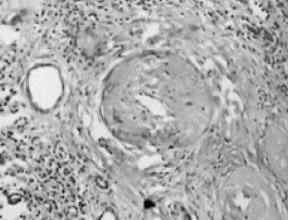

肾动脉狭窄最常见于肾动脉开口处或近端1/3血管,非开口处血管病变仅占15%~29%,肾动脉主干远端仅占5%。动脉粥样硬化引起的肾动脉狭窄主要累及大中动脉,动脉内膜粥样斑块,溃疡或血栓形成,多为双侧病变(见图5—1,图5—2)。

图5—2 肾动脉分支内膜增厚,管腔狭窄